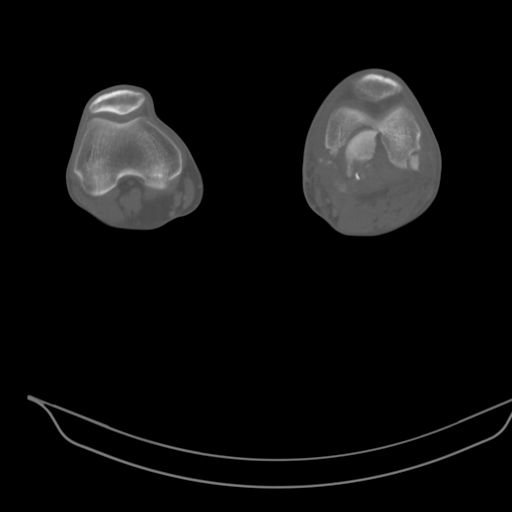

Качественные только исходные рентгенограммы (вышлю или завтра или в понедельник). Все последующие рентгенисследования были малоинформативны

(в т.ч. и последние снимки). КТ-исследование делалось 3 или 4 дня назад...

CT shows major bony fragments which are markedly rotated .With this amount of bony damage,you probably should attempt to get reasonably loooking knee with ORIF and thn if he needs a TKR due to pain a few years from now, then tleast you have something looking like a knee that you can replace rather than having to use revision knee for a primary TKR now. 4 weeks is not too long .what is the condition of soft tissues?

При внутрисуcтавных переломах трехмерные (3D) изображения, кроме красивого снимка, не дают полную информацию о состоянии отломков, самыми информативными являются корональные срезы на КТ и обычная длинная ренгенограмма конечности для сравнения оси конечности.

Фронтальные внутрисуставные переломы мыщельков бедра, так называемые Hoffa fracture, не частые, но встречающиеся переломы, в основном они связаны с травмой высокой энергией.

В зависимости от смещения рекомендуется сопоставление костных фрагментов с последующей жесткой фиксацией.

В вашем случае доступ будет медиальный, сопоставить развернутый медиальный мыщелок и фиксацию надо произвести в передне-заднем

направлении шурупами 4.5 мм в диаметре, углубив головку шурупов под хрящ, а поперечную фиксацию - межмыщелковыми шурупами. Желательно применить шурупы 6.3 мм в диаметре. Дополнительная Buttress technique пластина предотвратит перелом от скольжения.

Даже при сросшемся переломе мыщелка рекомендуется реконструктивная операция для предотвращения последующих варус или вальгус деформации.

Место образовавшего костного дефекта после разворота мышелка заполняется спонгиозной аутокостью. Костная пластика применяется даже

в свежем случае.

Под наркозом редрессация, ранняя разработка сустава после операции, нагрузка на конечность через 12 недель помогут удержать без коллапса

фиксацию и поможет больному восстановить функции конечности без артропластики коленного сутава.